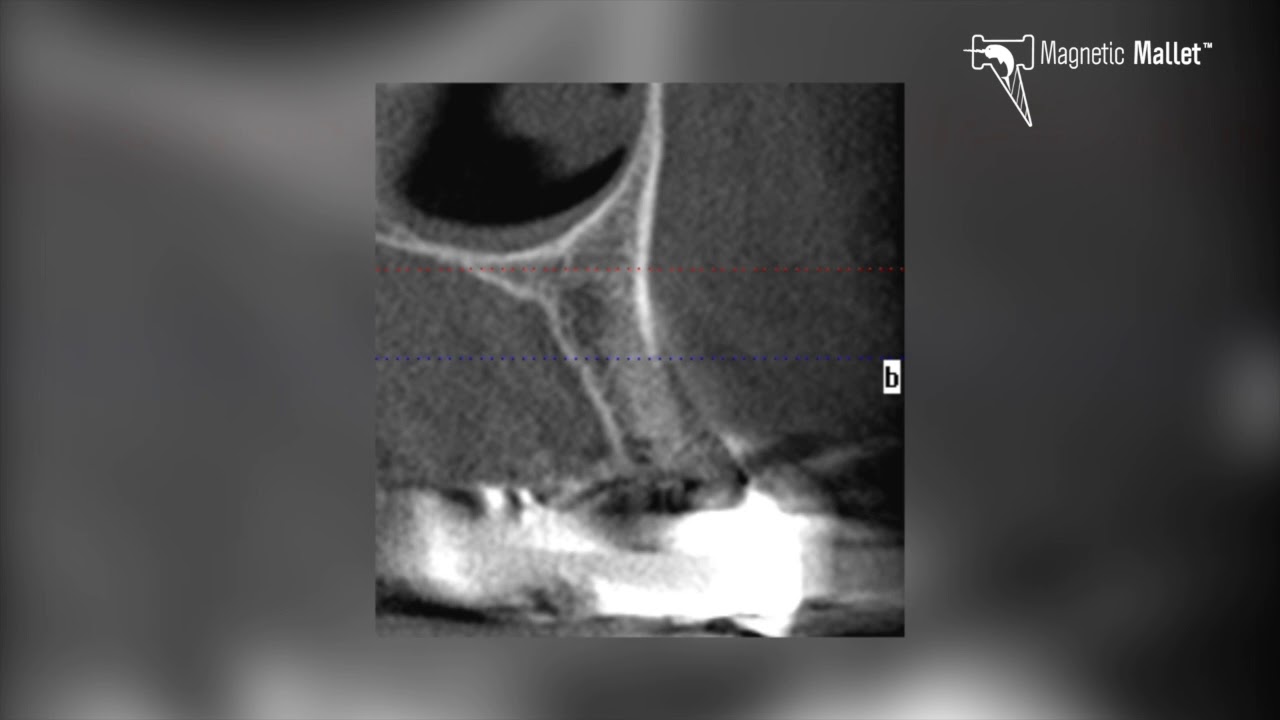

Figure 3 from Extraction followed by implant placement using Magnetic Mallet Extraction Magnetic dynamic technology allows you to perform even the most complex extractions without affecting soft tissues. The magnetic mallet is used for both routine surgical protocols as well as more advanced procedures where preserving bone allows. Each instrument can be reordered individually. Fourteen articles were included in this systematic review: The geometry of the instruments was designed to facilitate the. Magnetic Mallet Extraction.